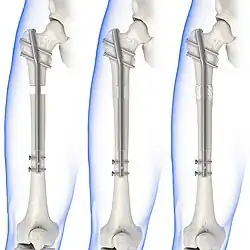

Internal fixators

Syndesmotic screws are the main, internal fixators used in surgeries for a Maisonneuve fracture. Two main types of syndesmotic screws are used: trans-syndesmotic screws (positioned at the level of the syndesmosis) and supra-syndesmotic screws (positioned above the syndesmosis).[14]

Based on several clinical results, syndesmotic screws are recommended to be fixed at least 1 centimetre proximal to the tibiofibular syndesmosis or 4 to 6 centimetres proximal to the tibiotalar joint line.[4][15] Cadaveric analyses, from a comparative study published in Foot & Ankle International in 1997, suggest that screw fixation at 2 centimetres proximal to the tibiotalar joint line is also adequate.[16] Biodegradable implants such as bioabsorbable screws, which do not require postoperative removal, may be used as an alternative to metallic hardware. However, biodegradable implants still limit rotation of the ankle and dorsiflexion of the foot.[4][6][13]

Following open-reduction, internal fixation is usually performed to stabilise the ankle mortise. To account for the distal fibula being slightly posterior to the distal tibia, drill holes are angled at 30° from the anteromedial aspect of the tibia to the posterolateral aspect of the fibula.[4][12][15] Trans-syndesmotic screws can be inserted in this way to ensure tibia fixation. Additional supra-syndesmotic screws may be temporarily inserted, for approximately 3 to 6 months, if instability is still present after fibular reduction. To reduce the fibula and restore the ankle mortise to its proper anatomical configuration, partial dorsiflexion of the foot is maintained prior to intraoperative screw fixation. This is because, in a neutral or maximally dorsiflexed position of the foot, the trochlear surface of the talus may reduce maximal postoperative dorsiflexion due to rigidity after screw fixation.[9][12]